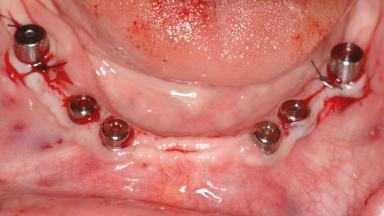

# of Implants 14

Bone Augmentation Horizontal|Sinus Floor Elevation|Staged|Vertical

Defining Characteristics Fully edentulous upper jaw to be rehabilitated with four or more implants

Modality Fixed hybrid bridge on 5+ implants

Bone Volume Deficient vertically or deficient vertically AND horizontally